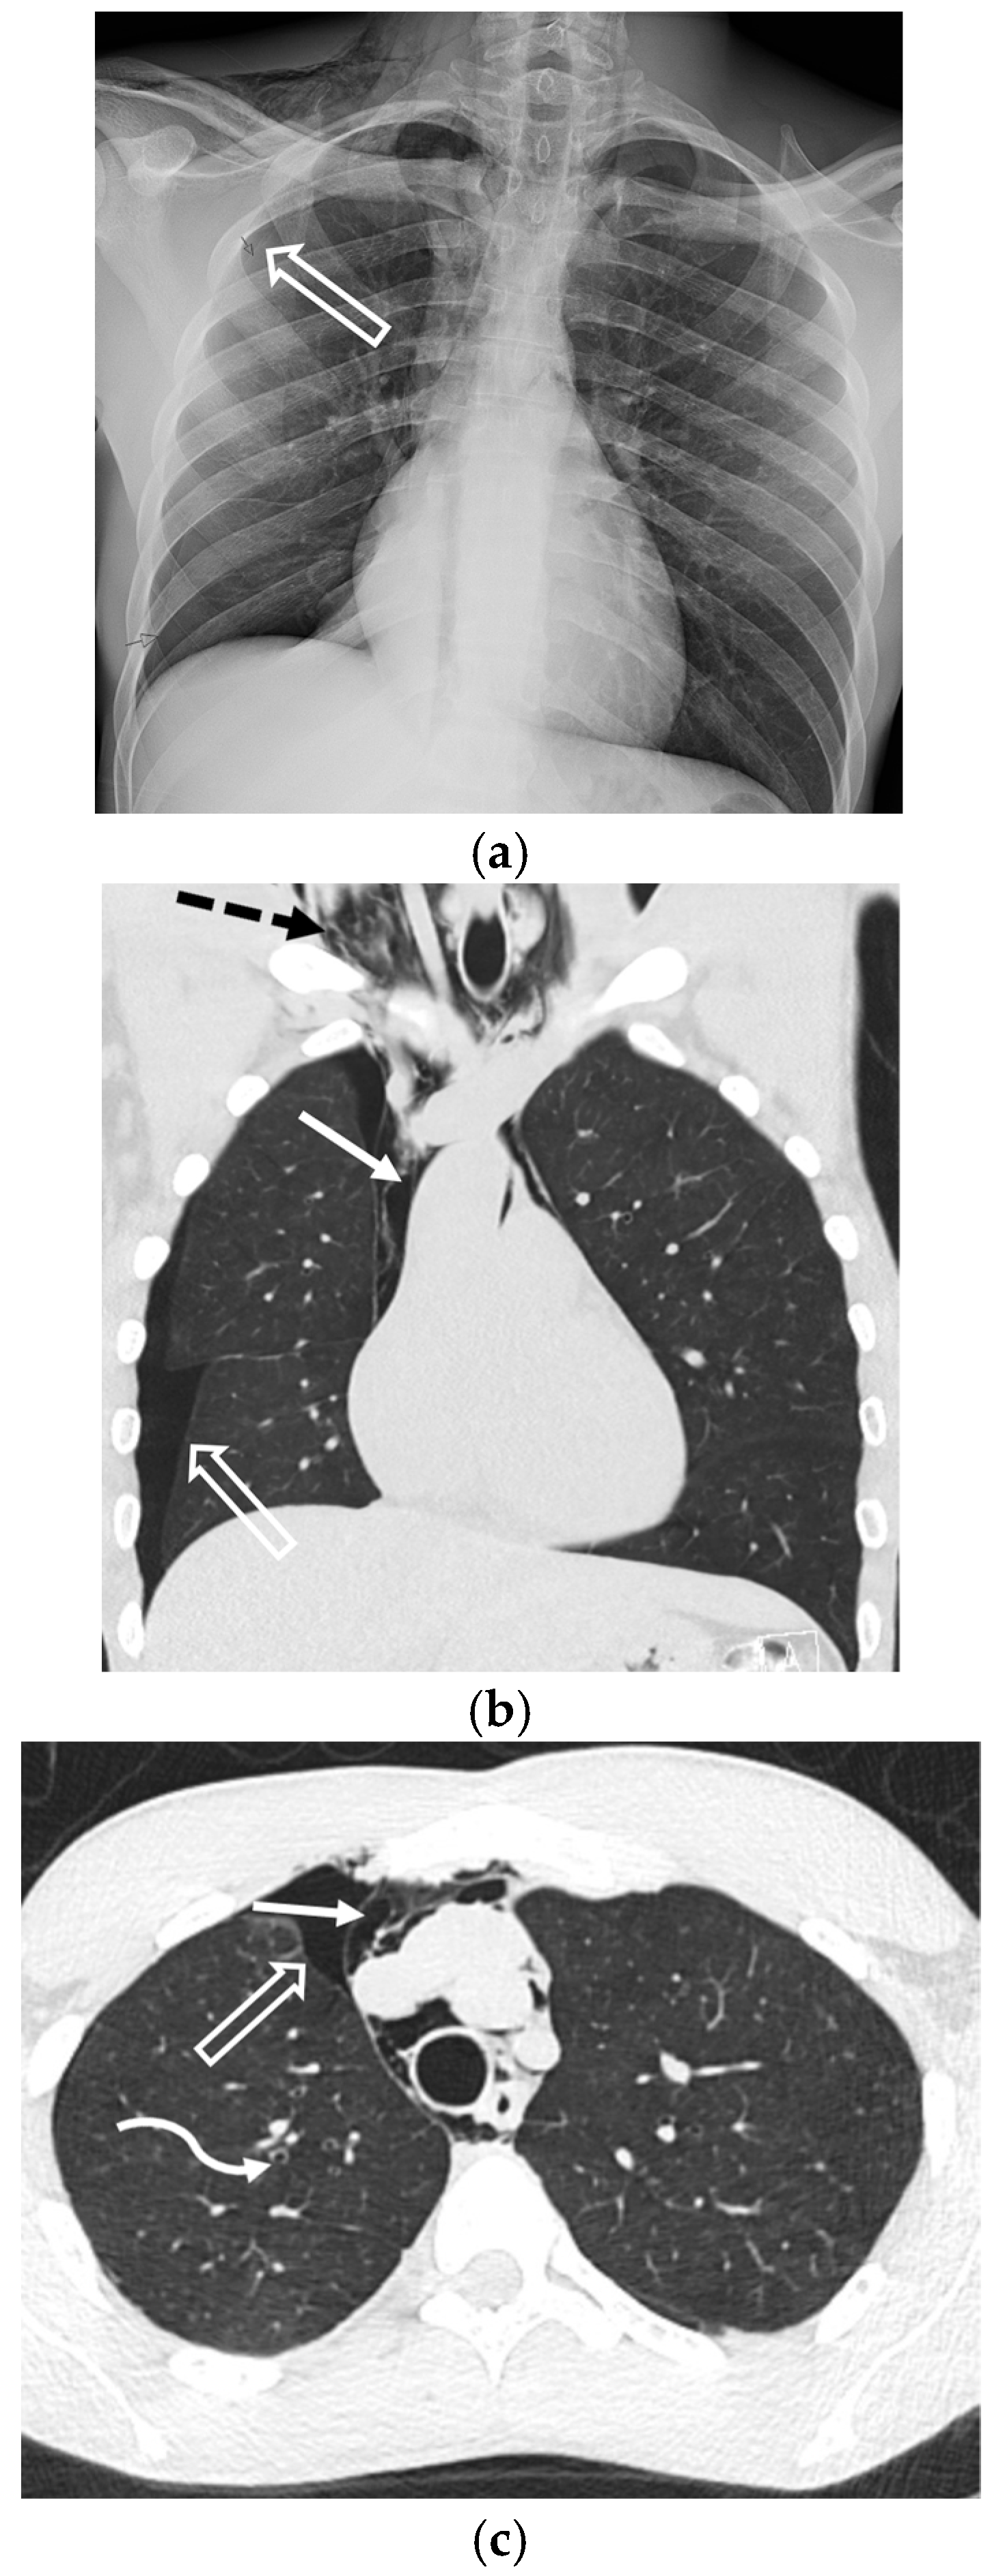

5.1.3. Pneumocystis jirovecii Pneumonia (PJP)

5.2.2. Cystic Fibrosis (CF)

5.5.1. Pulmonary Langerhans Cell Histiocytosis (PLCH)

5.5.2. Lymphangioleiomyomatosis (LAM)

5.5.3. Birt–Hogg–Dubé Syndrome (BHDS)